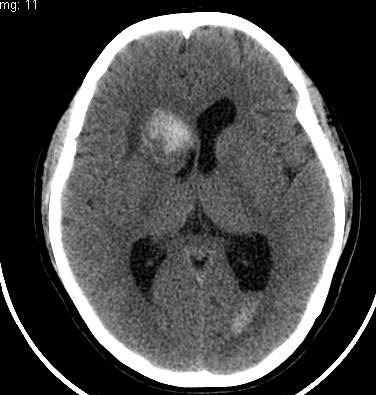

病史不详,右侧尾状核病灶出血,第二天做了颅脑ct增强,请大家帮忙看看如何诊断,谢谢!

支持考虑右侧尾状核头(或侧室前角室管膜下)出血,左侧室枕角有高密度影,考虑出血破入脑室

右侧尾状核头部出血破入脑室!